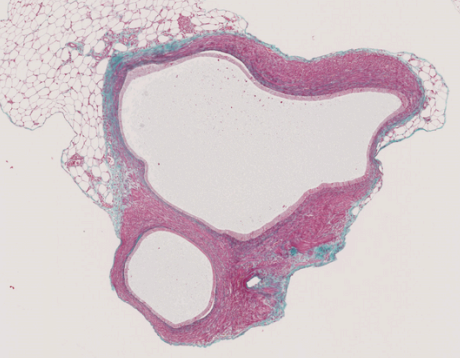

Endometriosis continues to pose a major clinical and scientific challenge—affecting millions worldwide yet still marked by late diagnoses, limited treatment options, and persistent misconceptions. While its underlying mechanisms span hormonal, immune, and genetic factors, therapeutic innovation has lagged behind. Here, we explore why current approaches fall short and how advanced preclinical platforms are enabling a more targeted, translational path forward.

- The molecular and immunological drivers that sustain chronic lesions